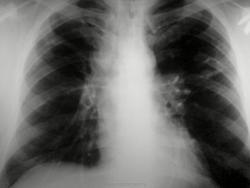

Потупил с диагнозом инфильтр tbs с поражением в/гр и периферич л/у. Болеет около месяца. Не контактен, пов t до 38. Менингиальные знаки 3+. Умер через 30 часов, на вскрытии...

Заподозрить еще как можно. Доказать, проблемно. Но подняв литературу узнал что картина типична для хронического... на фоне которого развивается... Обратите внимание на кисты слева, а справа формируется аналогичная.

Кавернозный туберкулез, ослабление иммуннитета. Присоединение неспецифической инфекции привело к сепсису и меннингиту, смерть, скорее, от менингита. Смущает эмфизема легких, но на легочную дистрофию не тянет. Конечно, досужие вымыслы. На КТ данных за медиастинит нет, кистовидные полости с толстыми стенками. СПИД всё бы объяснил.

Возраст около 45, точно не помню. На снимках еще стоял. Пока все мимо. Напомню увеличены в/гр и периферические л/у.